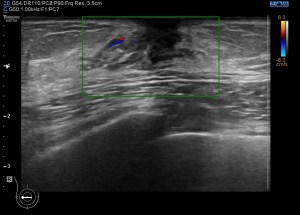

Siempre la anatomía normal. En la mujer tejido graso y tejido mamario conviven, en el hombre el tejido mamario no debe existir y tenemos que demostrar siempre la ausencia de este en el espacio retroareolar, principalmente. En la imagen 1 ves la relación de tejidos en un corte axial del pezón de la mama derecha masculina. Corresponde con la imagen número 2 ya sin anatomía.